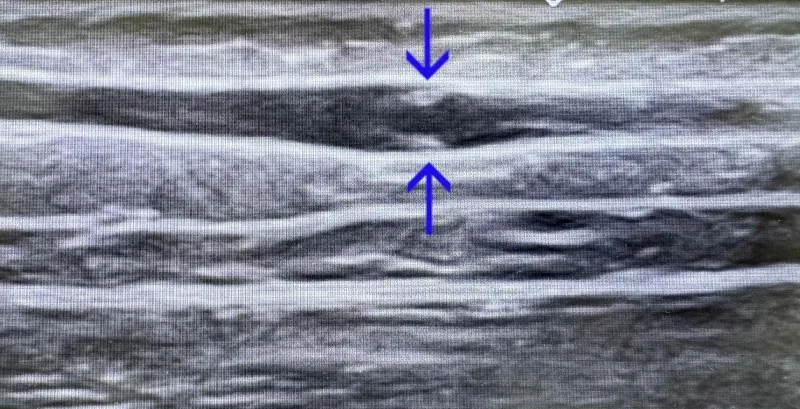

венозный клапан

Так выглядит нормальный венозный клапан в небольшом физиологическом расширении вены в виде двух лепестков